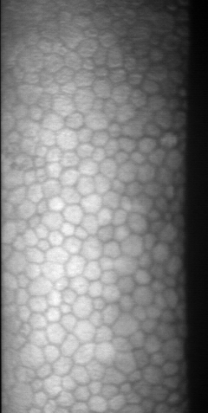

Specular microscopy assessment of the human corneal endothelium (CE) in Fuchs' dystrophy is challenging due to the presence of dark image regions called guttae. This paper proposes a UNet-based segmentation approach that requires minimal post-processing and achieves reliable CE morphometric assessment and guttae identification across all degrees of Fuchs' dystrophy. We cast the segmentation problem as a regression task of the cell and gutta signed distance maps instead of a pixel-level classification task as typically done with UNets. Compared to the conventional UNet classification approach, the distance-map regression approach converges faster in clinically relevant parameters. It also produces morphometric parameters that agree with the manually-segmented ground-truth data, namely the average cell density difference of -41.9 cells/mm2 (95% confidence interval (CI) [-306.2, 222.5]) and the average difference of mean cell area of 14.8 um2 (95% CI [-41.9, 71.5]). These results suggest a promising alternative for CE assessment.